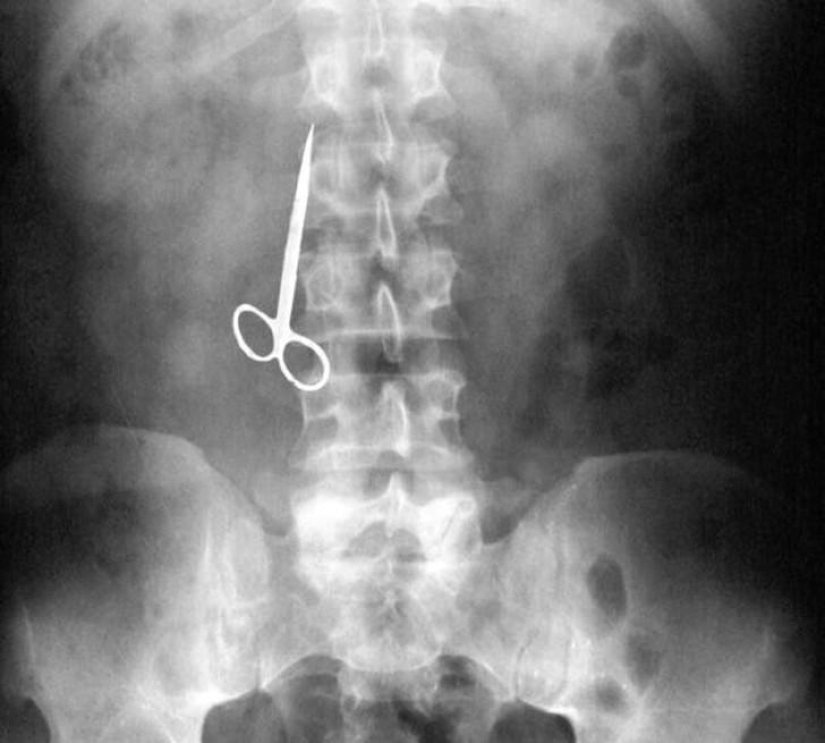

Tijeras.